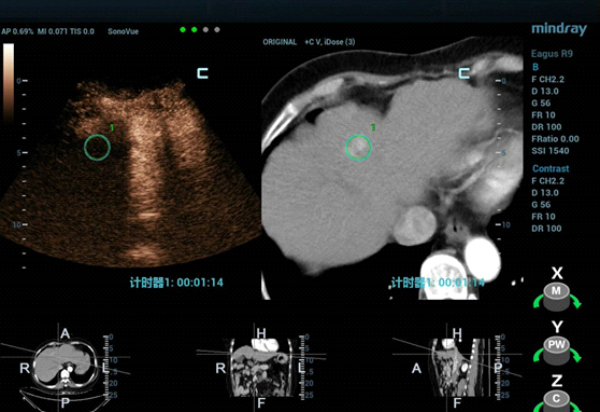

fusion-imaging-fig4

클립 1. 초음파 와 조영제 증강CT 융합 영상.

형태 4. 초음파와 CT영상 융합 후 CEUS(Contrast-Enhanced Ultra Sound)를 통해 종괴 위치를 재확인.